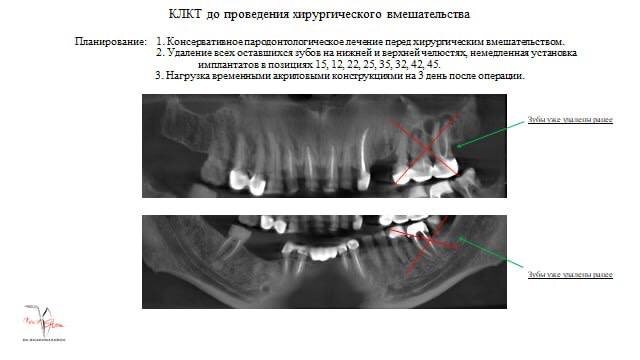

Тотальная реабилитация на имплантатах А2 rock Хирург-имплантолог: Шахназаров Эдгар Михайлович Ортопед: Магомедов Джамал Абдулнасирович Пациент Р. обратился в клинику с жалобами на частичное отсутствие зубов, трудности с пережевыванием пищи и нарушение эстетики. Учитывая пожелания пациента, было принято решение о тотальной реабилитацию на дентальных имплантатах, что позволило бы в сжатые сроки восстановить эстетику и функцию зубных рядов обеих челюстей. 1. Профессиональная гигиена полости рта. 2. Под медикаментозной седацией выполнено удаление зубов, установка дентальных имплантатов и фиксация временных конструкций. 3. После завершения остеоинтеграции изготовление и фиксация постоянных ортопедических конструкций.